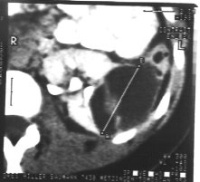

Die Computertomographie zur Bestimmung der Tumorausdehnung, zum Ausschluss einer zystischen Nierenfehlbildung (Differentialdiagnose) und zur Suche nach einem eventuellen kontralateralen Nierentumorbefall von Interesse. Außerdem dient das CT zur Flankierung der Chemotherapie (Ergebniskontrolle) (Abbildung 7,8,9).

(Die Abbildungen 7-8 wurden uns freundlicherweise von Herrn Dr. med. Günter Antes, Kempten überlassen)